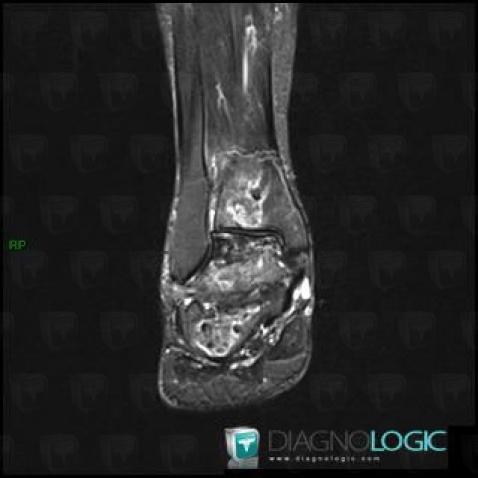

Avascular necrosis, Tibia - Distal part, MRI

Here is the specific information in the key image above:

- Diagnosis Avascular necrosis, Location(s) Tibia - Distal part, with gamuts Well-defined osteolysis, Epiphyseal osteolysis

- Diagnosis Gaucher disease, Location(s) Tibia - Distal part, with gamuts Mulltiple osteolysis

Avascular necrosis, Talus, MRI

- Diagnosis Avascular necrosis, Location(s) Talus, with gamuts T2 WI Hypointense bone lesion